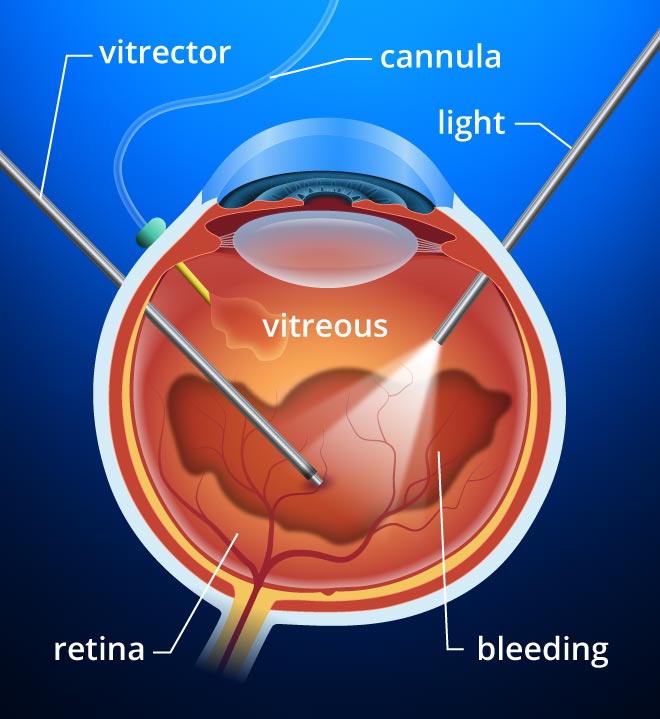

Vitrectomy And Vitreoretinal Eye Surgery Vitreous Hemorrhage Surgery

Vitrectomy And Vitreoretinal Eye Surgery Vitreous Hemorrhage Surgery

Vitrectomy Fraser Eye Care Center